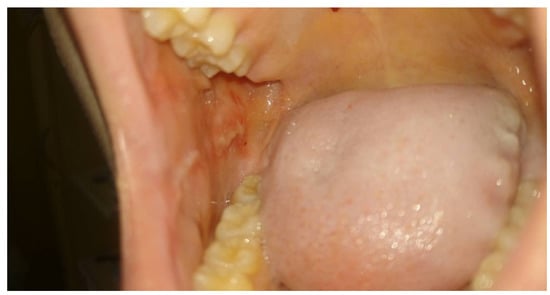

Moreover, a dependence between the state of the mucous membrane and peripheral blood parameters was observed. When there was a suppressed white cell count, the first symptoms of inflammation of the oral mucosa began to appear. However, parents, as well as experienced physicians and nurses, reported faster wound healing and better function of patients associated with PBM sessions even in cases of stagnated neutropenia or a significant decrease in the neutrophil count occurring during the OM episodes as presented in Figure 1 and Figure 2.

Figure 1. Intraoral photograph showing buccal mucosa with oral mucositis grade 3 (WHO scale) in a 15 year old girl, one week after methotrexate therapy, before PBM sessions, with a neutrophil count of 0.36 × 109/L. The patient was not able to eat solid foods, only liquids, with a pain level at VAS = 8.

Figure 2. The same patient after two PBM sessions (96 h later) with OM grade 1 (WHO scale), a neutrophil level of 0.43 × 109/L, and pain at VAS = 3, eating solid food.